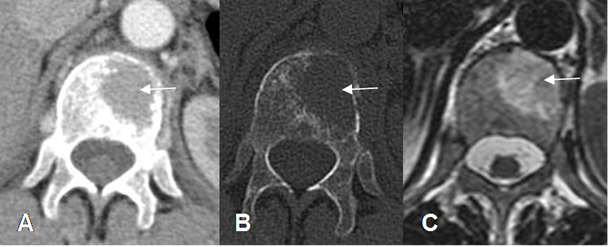

Fig 28. Mieloma múltiple.

A: TAC axial en ventana de tejido y B: en ventana de hueso. Lesión focal en el lado izquierdo del cuerpo vertebral, por plasmocitoma solitario.

C: RM axial en T2. La misma lesión hiperintensa en el cuerpo de D12.